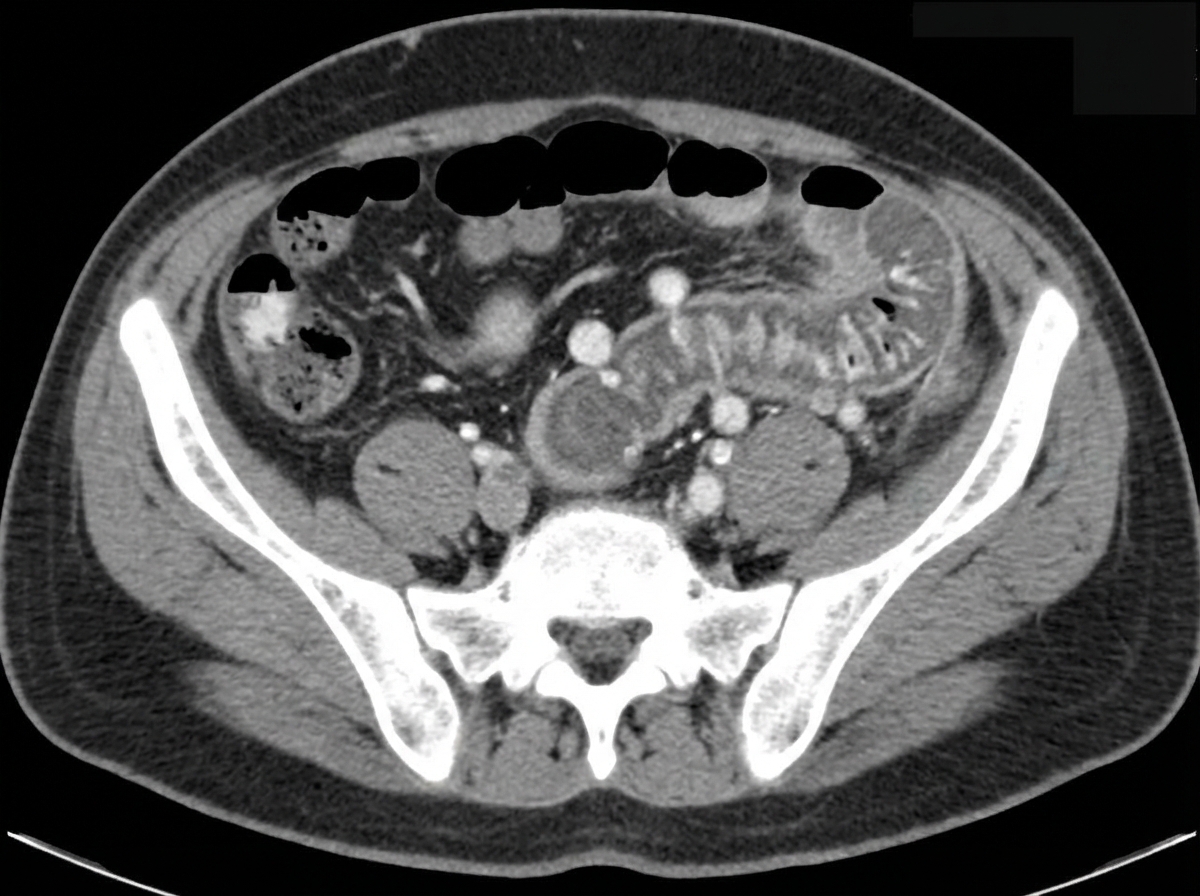

A 65-year-old man comes to the physician because of abdominal pain and bloody, mucoid diarrhea for 3 days. He has been taking over-the-counter supplements for constipation over the past 6 months. He was diagnosed with type 2 diabetes mellitus 15 years ago. He has smoked one pack of cigarettes daily for 35 years. His current medications include metformin. His temperature is 38.4°C (101.1°F), pulse is 92/min, and blood pressure is 134/82 mm Hg. Examination of the abdomen shows no masses. Palpation of the left lower abdomen elicits tenderness. A CT scan of the abdomen is shown. Which of the following is the most likely underlying cause of the patient's condition?

Explanation: **Focal weakness of the colonic muscularis layer** - The patient's symptoms of **abdominal pain**, **bloody, mucoid diarrhea**, and **left lower abdominal tenderness** are classic for **diverticulitis**, which occurs when small pouches (diverticula) in the colon become inflamed or infected. Diverticula form due to **focal weakness in the colonic muscularis layer**, often at points where blood vessels penetrate the muscle wall. - **Constipation** and a history of **smoking** are risk factors for diverticular disease, contributing to increased intraluminal pressure and the formation of diverticula. *Twisting of the sigmoid colon around its mesentery* - This describes a **sigmoid volvulus**, which presents with acute onset of **severe abdominal pain**, distension, and obstipation (complete absence of stool and gas). - While a volvulus can cause bloody stools due to ischemia, the clinical presentation and likely CT findings (not provided, but inferred to show diverticula) are inconsistent with this condition, and the described symptoms point more towards inflammation. *Transmural inflammation of the terminal ileum* - This suggests **Crohn's disease**, which can cause abdominal pain and diarrhea. However, Crohn's disease typically affects the **terminal ileum** and has a more chronic course, often with weight loss, perianal disease, and extraintestinal manifestations. - Bloody, mucoid diarrhea is less typical for Crohn's unless there is severe colonic involvement, and the acute onset and tenderness in the left lower quadrant point away from isolated terminal ileitis. *Infiltrative growth in the descending colon* - An **infiltrative growth** (e.g., colorectal cancer) can cause changes in bowel habits, abdominal pain, and bloody stools. However, it usually presents with more **chronic symptoms** and weight loss. - The acute inflammatory picture presented (fever, tenderness, mucoid diarrhea) is less characteristic of an uncomplicated infiltrative growth without obstruction or perforation. *Decreased perfusion to mesenteric blood vessel* - This describes **ischemic colitis**, which causes acute abdominal pain, bloody diarrhea, and tenderness. While it's a possibility, especially in older patients with vascular risk factors (diabetes, smoking), the description of **mucoid diarrhea** and the strong association with a history of constipation and symptoms pointing to localized inflammation (tenderness in left lower abdomen suggesting sigmoid/descending colon involvement) make **diverticulitis** a more likely primary cause in this context unless imaging strongly suggests ischemia. - Ischemic colitis often presents with more severe, diffuse abdominal pain often out of proportion to physical exam findings initially.